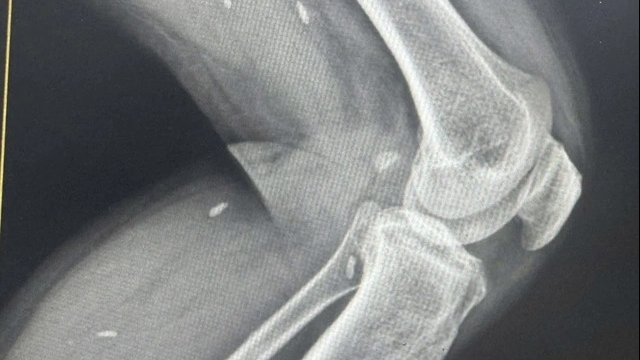

Kết quả xét nghiệm tại BV Ung bướu Hà Nội cho thấy, bệnh nhân bị đa u mỡ, lan tỏa toàn bộ vùng cổ, nền cổ, thượng đòn hai bên, chỗ dày nhất bên phải kích thước 12 cm và bên trái 13 cm. U chèn ép lên khí quản, thực quản chính là nguyên nhân gây khó thở, nuốt nghẹn.

Bác sĩ chỉ định bệnh nhân phải phẫu thuật cắt bỏ khối u. Sau 2 giờ phẫu thuật, nhiều khối u mỡ được cắt bỏ có cân nặng lên tới 2 kg, khí quản, thực quản được giải phóng khỏi chèn ép.

TS Đàm Trọng Nghĩa, Trưởng khoa Ngoại đầu cổ, BV Ung bướu Hà Nội chia sẻ, nam bệnh nhân có tiền sử bệnh tim mạch, men gan cao nên quá trình gây mê khá phức tạp. Tổ chức mỡ lan tỏa rộng, bao toàn bộ khí quản, thực quản nên khi phẫu thuật phải tính toán để tránh những nguy cơ nguy hiểm như tổn thương khí quản, thực quản, các mạch máu lớn, dây thần kinh vùng cổ.

Đặc biệt, nếu bác sĩ cắt quá rộng có thể gây hoại tử vạt da. Vì vậy, để loại bỏ hết các khối u mỡ, bệnh nhân cần phải phẫu thuật nhiều lần.